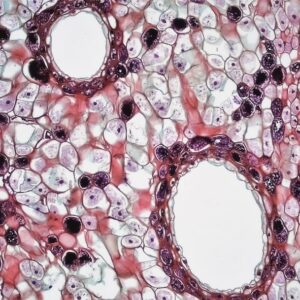

Photo Microscopic view

Pathology Outlines Small Cell Carcinoma

Small cell carcinoma, often referred to as small cell lung cancer (SCLC), is a highly aggressive form of cancer that primarily originates in the lungs but can also manifest in…